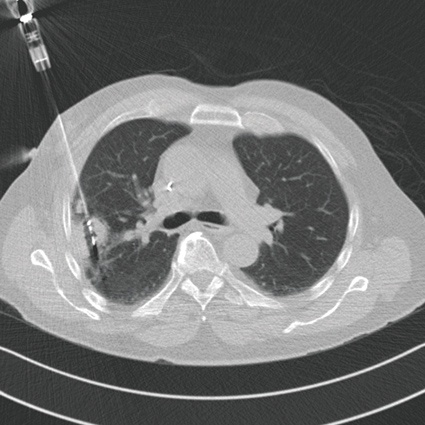

Das neue Gebiet der interventionellen Onkologie fasst Therapieverfahren zusammen, die auf dem interventionell bildgebend gesteuerten Einsatz modernen Therapieverfahren beruhen. Darunter gehören Thermoablationsverfahren wie die Lasertherapie (LITT), die Mikrowellenablation (MWA) und die Radiofrequenzablation (RFA). Ergänzt wird das Teilgebiet der interventionellen Onkologie durch Therapieverfahren wie regionale Chemotherapie und Embolisation, dies erfolgt einmal über das Lungengefäßsystem der Vasa privata, über die Bronchialarterien als Bronchialarterienembolisation und auch als Chemoembolisation über das Versorgungsgebiet der pulmonalen Arterien in Form einer pulmonalarteriellen Chemotherapie mit Perfusion, Okklusion und Embolisation (TPCE).

Das neue Verfahren der Mikrowellenablation stellt insgesamt eine Weiterführung der bisherigen Therapiestrategien basierend auf der monopolaren oder bipolaren Radiofrequenztherapie (RFA) dar. Der Vorteil der Mikrowellenablation liegt dabei in der schnelleren Durchführbarkeit, der höheren Effizienz und den fehlenden Limitationen der physikalischen Energieausbreitung wie bei der RFA. Daraus resultiert ein insgesamt höheres Ablationsvolumen und eine verbesserte Therapiekontrolle.

Die Indikationsstellung umfasst derzeit für die percutane Thermoablation mittels Mikrowellenablation Patienten, die nicht mehr resektabel sind, Patienten, die durch die Intervention in eine resektable Situation überführt werden können, die Anzahl der Herde sollte dabei eine Zahl von ≤ 3 nicht überschreiten, die Größe der Herde ≤ 3 max. 4 cm.

Zielsetzung der Mikrowellenablation (und weiteren Ablationstechniken) ist die komplette Destruktion aller vitalen Tumorzellen im Zielvolumen mit einem Sicherheitssaum, Minimierung der Schädigung von Umgebungsstrukturen. Die möglichen Vorteile gegenüber einem chirurgischen Verfahren liegen in der hohen Ortspräzision und dem selektiven Zugangsweg und einer minimal-invasiven Behandlungsstrategie mit tagesstationärer Durchführbarkeit und einer geringeren Belastung des umgebenden normalen Lungenparenchyms. Die Grundlage der Therapie ist dabei die Erzielung einer Temperaturerhöhung intratumoral und in den Sicherheitszonen zwischen 80 und 100 Grad Celsius und geht in der Regel einher mit einer kompletten Destruktion von Zellanteilen wie den Mitrochondrien im Zytoplasma und weiteren Leitstrukturen.